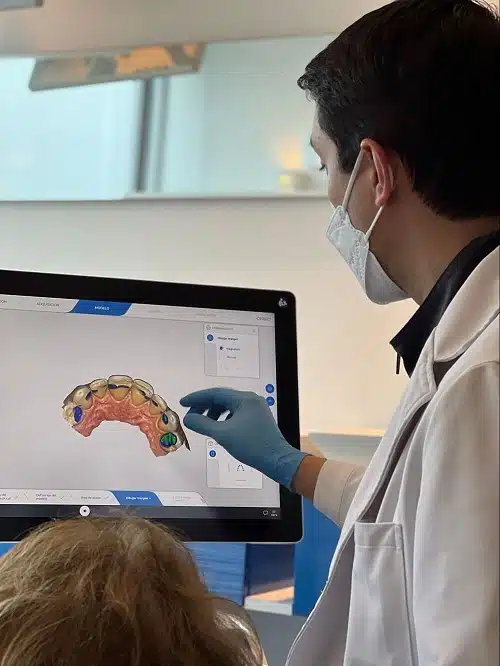

Diseño de Sonrisa

El Diseño de Sonrisa es un concepto que refleja la creación de una nueva sonrisa, funcionando en armonía con sus características faciales, realizado a través de un software 3D de última generación.

Durante la última década, el término diseño de sonrisa se ha convertido poco a poco en el más utilizado en la odontología estética y es cada vez más popular. Mayor información aqui 🙂